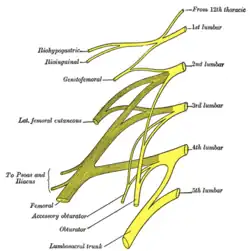

The posterior divisions of the sacral nerves. Plan of lumbar plexus.

Plan of lumbar plexus. Cutaneous nerves of the right lower extremity. Front and posterior views.

The subcostal nerve (anterior division of the twelfth thoracic nerve[1]) is a mixed motor and sensory nerve contributing to the lumbar plexus. It runs along the lower border of the twelfth rib, often gives a communicating branch to the first lumbar nerve, and passes under the lateral lumbocostal arch.

It communicates with the iliohypogastric nerve and the ilioinguinal nerve of the lumbar plexus,[1][2] and gives a branch to the pyramidalis muscle and the quadratus lumborum muscle.[3] It also gives off a lateral cutaneous branch that supplies sensory innervation to the skin over the hip.